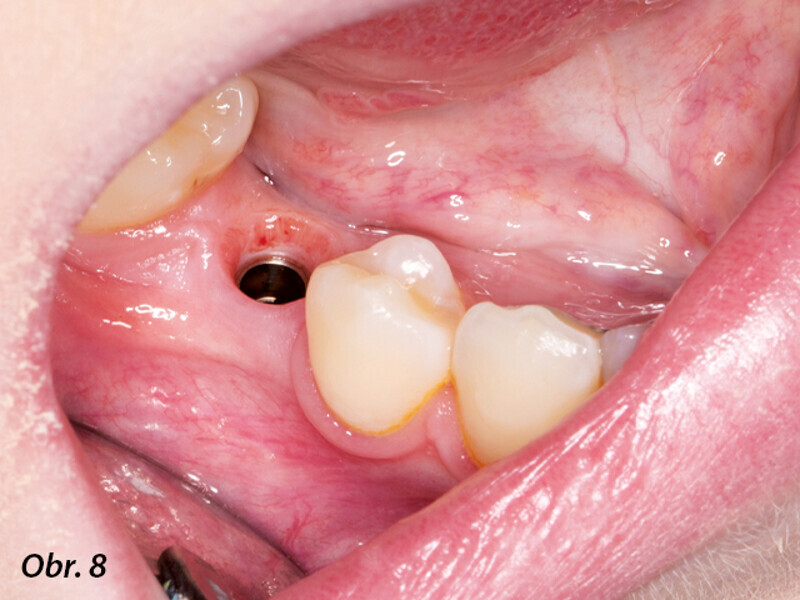

Řízená implantologie za použití řešení Planmeca all-in-one